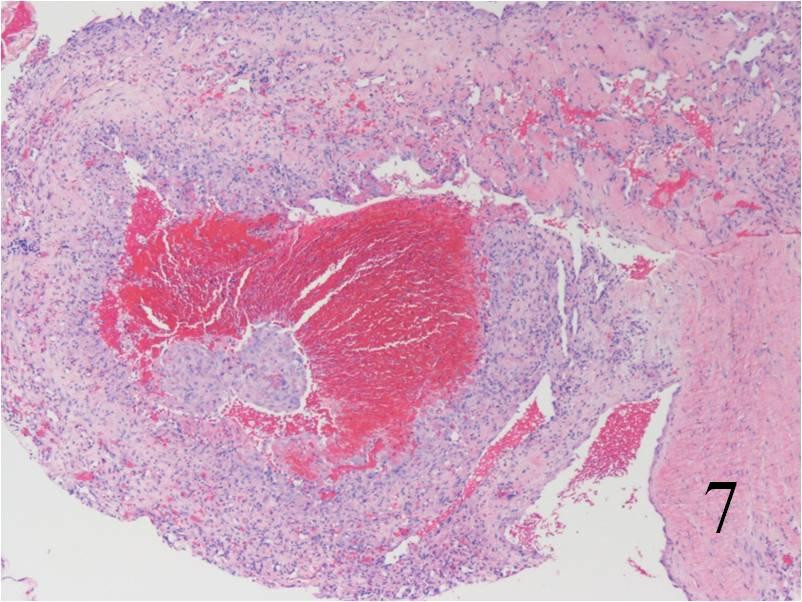

Fig. 7

Fig. 7-8: Microscopic: Low (Fig. 7) and high (Fig. 8) power histology of an angiosarcoma shows abundant round to polygonal tumor cells. Fig. 8 shows nuclear atypia with mitotic activity. The cells are large with large irregular nuclei and significant pleomorphism. The cells appear somewhat epithelioid. The tumor stains positive for vimentin, Factor VIII and CD 34 (not shown in these photographs)